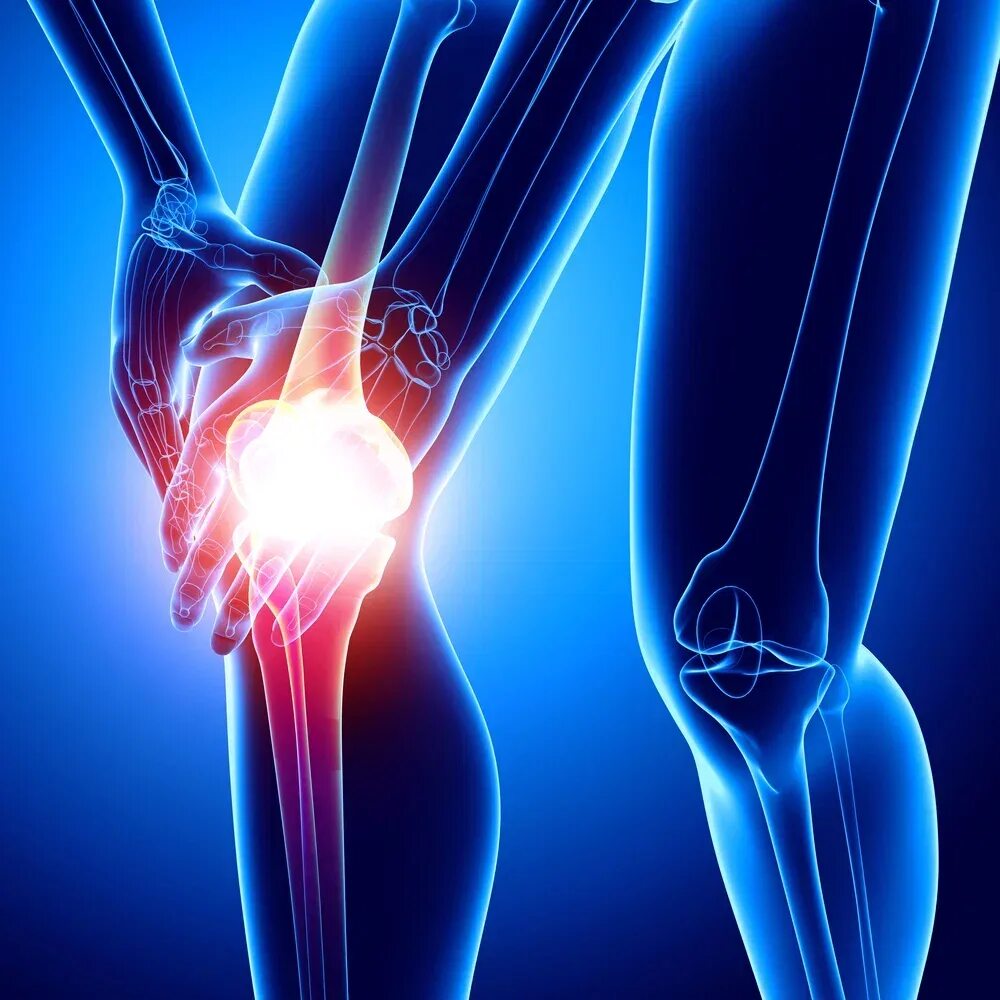

Ревматизм ног